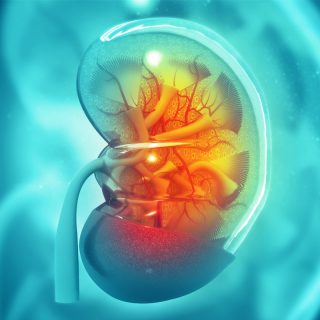

OUR KIDNEY

The kidneys are located on the back of the body cavity, on both sides of the spine. Our organs are 10-12 cm long, whose shapes resemble beans.

KIDNEY FUNCTIONS

Keeping the salt and water balance in the body and keeping various minerals in the blood at a constant level. To discharge waste products from the body

KIDNEY FAILURE

The kidney is an organ weighing 100-150 grams located in the posterior region of the abdomen. Normal people have two kidneys, right and left.